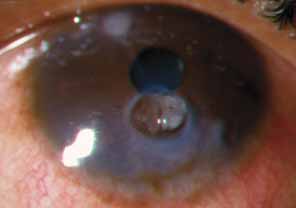

The current number of procedures performed on an annual basis is decreasing slightly; a total of 32,744 corneal transplants were performed in 2002, marking the first time since 1986 that the number of procedures performed has been less than 33,000.1 This downward trend has coincided with the decrease in incidence of pseudophakic corneal edema (PCE) (Fig. 1) and aphakic corneal edema (ACE). The percentage of PKs performed to treat PCE has dropped from 19.8% in 2001 to 18.4% in 2002, which was the lowest percent reported in this category in 15 total years of tracking by the Eye Bank Association of America (EBAA). It is possible that this decrease reflects improved cataract removal technique and technology, such as phacoemulsification and posterior chamber intraocular lens placement. The indications for PK have shifted over the past several decades, with PCE the most common indication since 1980, whereas keratoconus (Fig. 2) and ACE were the most common indications prior to 1980.2 Data is tracked for a total of 16 indications for transplant by the EBAA. Pseudophakic corneal edema, keratoconus (particularly in younger patients), Fuchs' endothelial dystrophy (particularly in older patients), and regrafting secondary to rejection or other reasons currently sit atop the list of indications for PK.

Fig. 1 Pseudophakic corneal edema is the leading indication for penetrating keratoplasty in the United States.